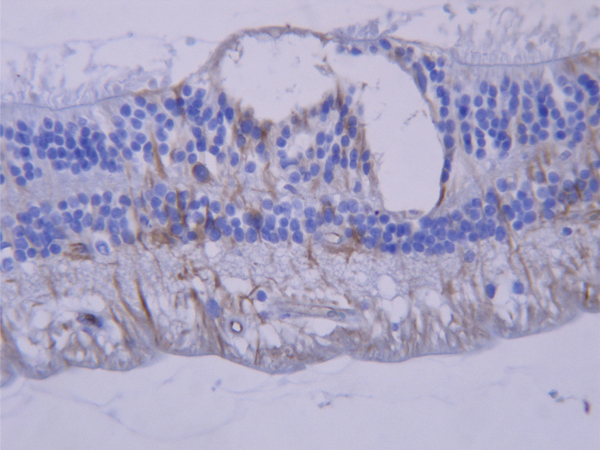

Les cellules de Müller ont un rôle métabolique et de maintien de l’architecture rétinienne. Elles expriment en immuno-histochimie la glial fibrillary acidic protein ou GFAP (fig. 2-10).

Fig. 2-10 Marquage par la GFAP (brun) des cellules de Müller et des astrocytes.

Comme dans le cerveau, il s’agit de cellules stellaires à noyau ovale. Ils sont surtout abondants dans la couche des fibres nerveuses et autour des vaisseaux. Ils expriment aussi la GFAP (fig. 2-10).